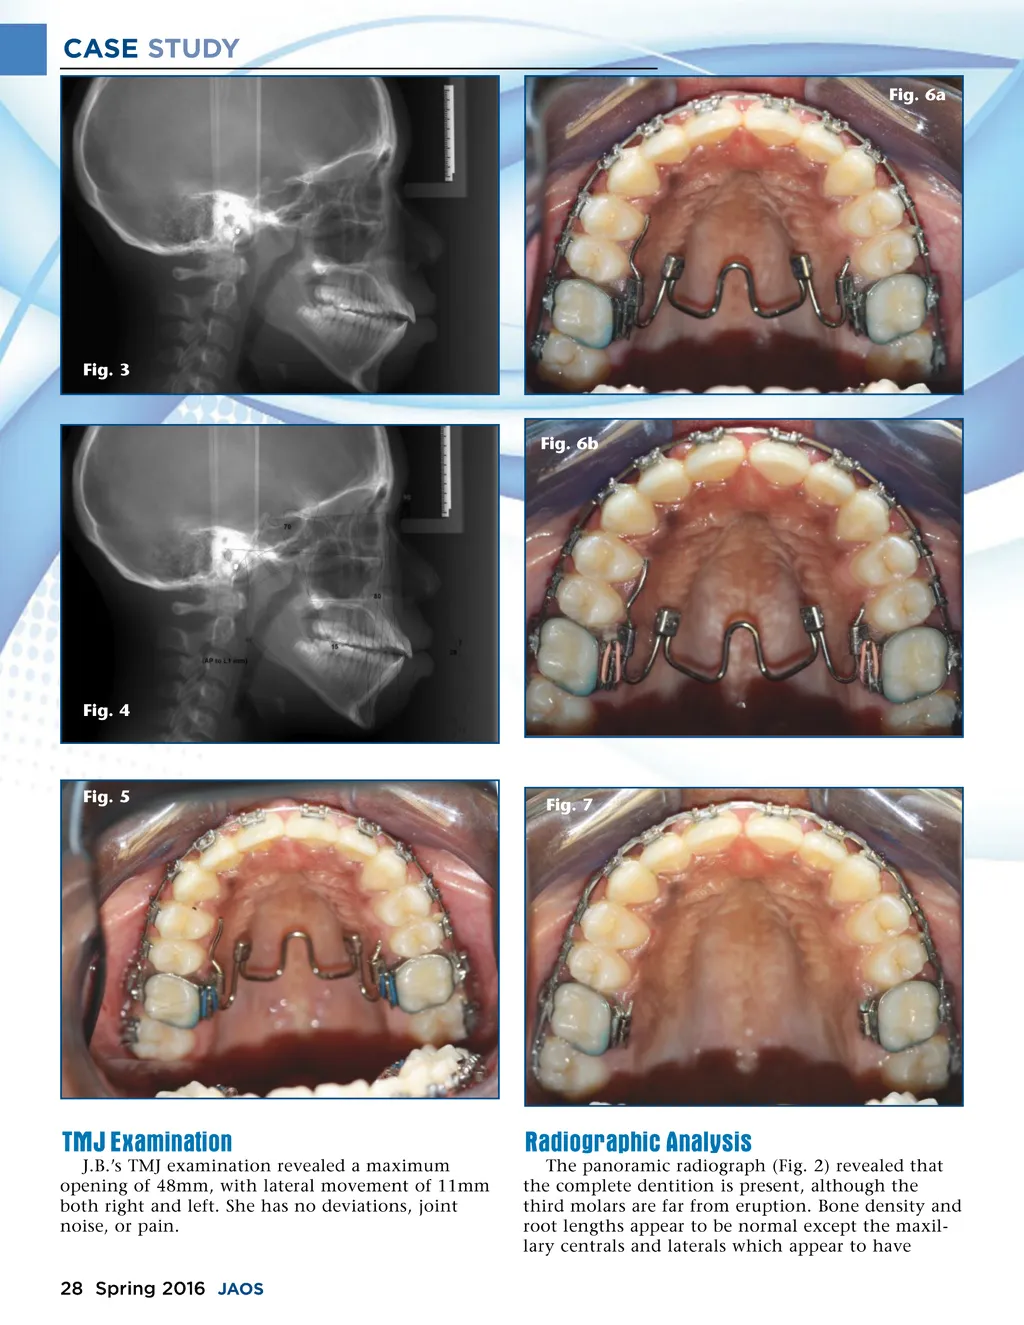

CASE STUDY Fig. 6a Fig. 3 Fig. 6b Fig. 4 Fig. 5 Fig. 7 TMJ Examination J.B.’s TMJ examination revealed a maximum opening of 48mm, with lateral movement of 11mm both right and left. She has no deviations, joint noise, or pain. Radiographic Analysis The panoramic radiograph (Fig. 2) revealed that the complete dentition is present, although the third molars are far from eruption. Bone density and root lengths appear to be normal except the maxil-lary centrals and laterals which appear to have 28 Spring 2016 JAOS